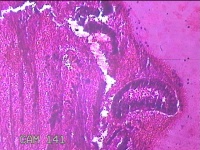

宫颈管组织

性别

女

年龄

41岁

临床诊断

子宫腺肌症并腺肌瘤 子宫异常出血 贫血

一般病史

月经量多2年余。

标本名称

宫颈管痔组织

大体所见

纱布一块,内有灰白暗红色不规则碎组织0.8x0.5x0.3cm一堆。